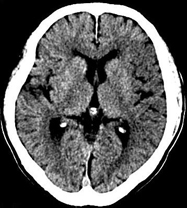

如上圖所示,相鄰的三張軸位圖像未見明顯異常,根據(jù)傳統(tǒng)軸位圖像很難得到準確的臨床診斷。

同一病人利用容積數(shù)據(jù)進行三維處理后,高品質MPR和三維圖像上則清晰顯示了縱向排列的腹腔干與腸系膜上動脈相鄰近,血管發(fā)生變 異,近端血管閉塞,為臨床提供了精確的診斷信息。

從上面的例子可以看到,能否為臨床提供高品質的三維影像成為了16層CT的核心價值,而東芝新一代的 全景三維16層CT擁有最為  先進的3項核心技術,在16層核心價值上的表現(xiàn)自然值得期待。